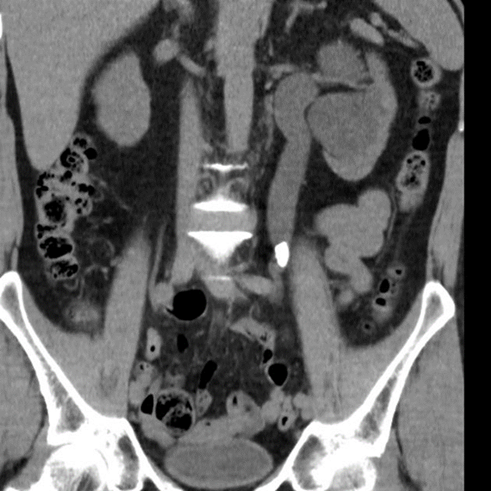

Vad ses på bilden?

A

Samlingssystemet med uttalad hydronefros, uttalad hydrouretär ned till konkrement i övergång mellan proximal uretär och mellersta delen ureätär

DT visar

• Samlingssystemet med uttalad hydronefros, uttalad hydrouretär ned till konkrement i övergång mellan proximal uretär och mellersta delen ureätär